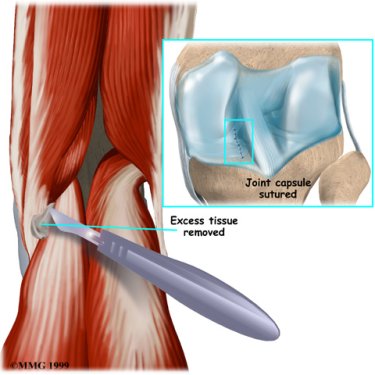

The goal of surgery is to remove the cyst and repair the hole in the joint lining where the cyst pushed through. Unfortunately, about half of the time the cyst comes back, or recurs, after being removed. Surgeons are cautious when suggesting surgery to remove a popliteal cyst because they are prone to recur. The cure is often permanent, but preventing further cysts depends a great deal on the success of treating the underlying cause. You should be aware that there is a very real chance that your cyst may return after being removed and there is no guarantee that the surgery will be successful.

An incision will be made in the skin over the cyst.

An incision will be made in the skin over the cyst.

The cyst is then located and separated from the surrounding tissues. The area of the joint capsule where the cyst appears to be coming from is identified.

A synthetic patch may be sewn in place to cover the hole in the joint capsule left by the removal of the cyst.

Your knee will be bandaged with a well-padded dressing and a splint for support.